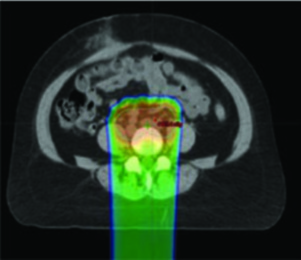

Para o tratamento definitivo, a dosimetria-alvo deve ser idêntica à utilizada com fótons, corrigida pela efetividade biológica relativa (RBE) assumida de 1,1 para prótons. O delineamento de GTV e CTV segue os mesmos princípios do capítulo de EBRT definitiva. Os PTVs são específicos por feixe, baseados na incerteza de alcance. Um cuidado fundamental: evitar arranjos de feixe que coloquem estruturas críticas no campo distal ao alvo.

A terapia com prótons pode ser considerada como alternativa de boost para pacientes que não podem receber braquiterapia. Prótons apresentam vantagens dosimétricas em bexiga, intestino, cabeças femorais e reto em comparação ao VMAT. O CTV de boost pode ser determinado por RM obtida após 3 semanas de quimiorradiação, administrando-se então 30 Gy/Gy equivalente em 5 frações em substituição à braquiterapia. Entretanto, evidência prospectiva de alta qualidade ainda é insuficiente, e a relação entre dosimetria melhorada e redução clinicamente significativa de toxicidade permanece sem comprovação definitiva.

Cenários em que prótons podem oferecer vantagem sobre IMRT incluem tratamento de linfonodos para-aórticos e reirradiação. Estudos dosimétricos e clínicos iniciais mostram melhora na dose em estruturas normais adjacentes, incluindo intestino, bexiga e medula óssea. Prótons também permitem melhor preservação ovariana em mulheres pré-menopáusicas — por exemplo, poupando um ovário com dose média inferior a 15 Gy.